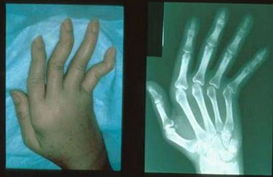

晚期风湿的危害二、变形致残

类风湿性关节炎病人前期会出现关节肿痛难受、僵硬,如果不及时 治疗轻则关节畸形,重则瘫痪,生活不能自理,让人生不如死。>>>了解更多关于风湿的危害,可以点击免费咨询专家